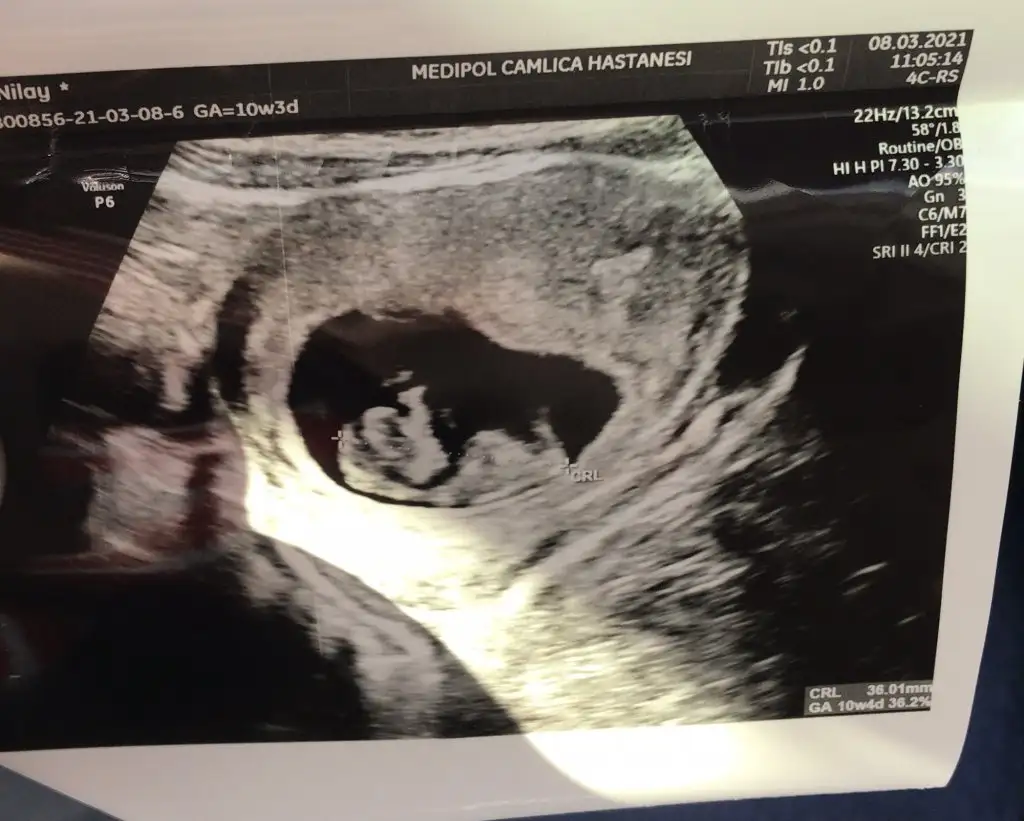

Kizlar benimki 11 haftalık şuan erkeğe benzettim dedi öbür ay net belli olur dedi sizce doğru olabilir mi ikili testi de verdik şükür

16. Haftada netlesir diyor doktorlar, değişiklik olabilir bence hazırlıklı olunKizlar benimki 11 haftalık şuan erkeğe benzettim dedi öbür ay net belli olur dedi sizce doğru olabilir mi ikili testi de verdik şükür

Belli olmaz. Oğlumda 11+3 de söyledi doktor doğru çıktı. Ama sonradan değişen de çok. Yanılma oranı çok yüksek bu erken haftalarda. En iyisi beklemekKizlar benimki 11 haftalık şuan erkeğe benzettim dedi öbür ay net belli olur dedi sizce doğru olabilir mi ikili testi de verdik şükür

Bende şok oldum hiç beklemiyordum sormadım bile direk öyle söyledi kıpır kıpır çok hareketliydi16. Haftada netlesir diyor doktorlar, değişiklik olabilir bence hazırlıklı olun![]()